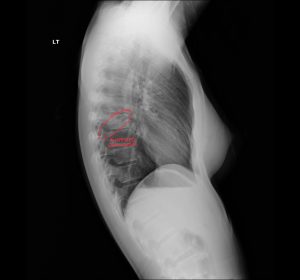

Right mid-lung field pneumonia manifests as a focal or segmental airspace opacity in the right mid-zone that increases pulmonary density and obscures adjacent vessels, often demonstrating air bronchograms without obligatory heart or diaphragmatic silhouette loss.

Consolidation pattern is typically homogeneous airspace filling, with preserved overall lung volume unless there is concomitant atelectasis or bronchial obstruction.

In a 30-year-old female, a new right mid-lung field opacity with cough is most consistent with community-acquired pneumonia, especially in the setting of acute or subacute respiratory symptoms. Patients frequently describe productive or dry cough, low-grade fever, pleuritic chest discomfort, and exertional dyspnea, though young adults can retain relatively preserved functional capacity and may present with a clinical picture akin to “walking pneumonia.” Physical examination typically reveals localized crackles, bronchial breath sounds, or egophony over the mid-right chest, corresponding to the radiographic opacity.

On chest radiography, normal lung appears relatively lucent because of its air content, while any process that replaces air with fluid, cells, or tissue increases local x-ray attenuation and appears as an opacity. This may reflect airspace filling (exudate, edema, hemorrhage), interstitial thickening (fibrosis, edema, inflammation), or atelectasis with reduced aeration. In the right mid-lung field, a focal opacity may therefore correspond to pneumonia, atelectasis, neoplasm, hemorrhage, or focal edema, so pattern recognition and careful search strategy are essential.

Pneumonia usually appears as a hazy, dense area obscuring vessels and sometimes showing air bronchograms.

On chest radiography, mid-field pneumonia manifests as an ill-defined homogeneous opacity that obscures normal vascular margins and may contain air bronchograms, reflecting exudate-filled alveoli traversed by aerated bronchi. Overall lung volume is often preserved, distinguishing it from segmental atelectasis, and a Chiropractic radiologist DACBR can highlight these features in a detailed Second opinion Radiology Report.